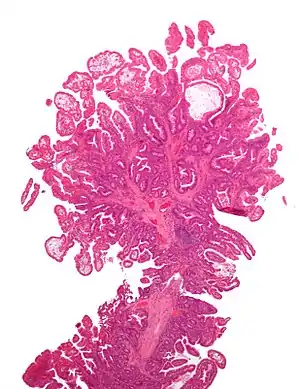

| Hyperplastic polyp | Colorectal (unless otherwise specified) | Serrated unbranched crypts | if polyps are more than 100 | ![]() |

Serrated polyposis syndrome |